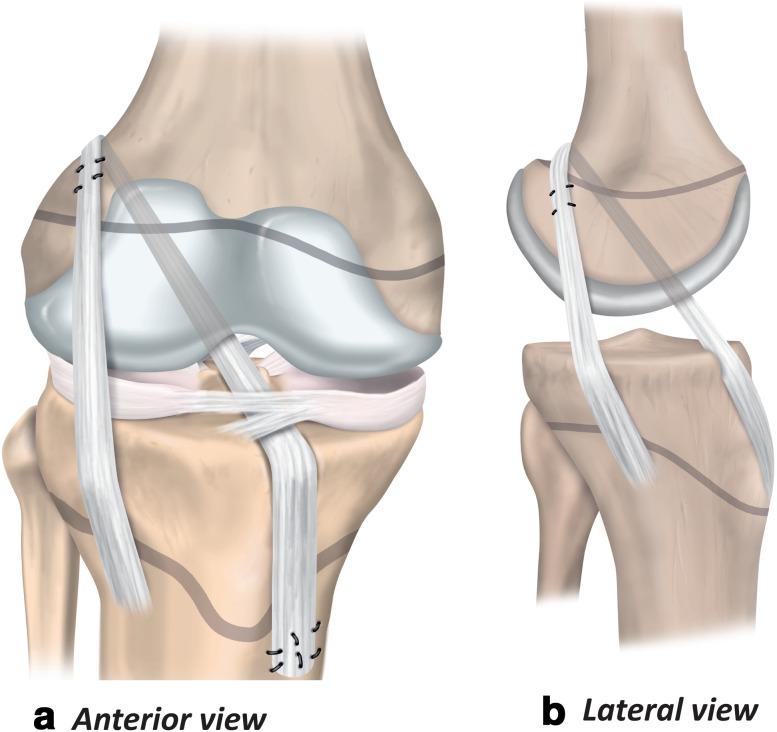

In October 2017, the International Olympic Committee hosted an international expert group of physiotherapists and orthopaedic surgeons who specialise in treating and researching paediatric anterior cruciate ligament (ACL) injuries. Representatives from the American Orthopaedic Society for Sports Medicine, European Paediatric Orthopaedic Society, European Society for Sports Traumatology, Knee Surgery and Arthroscopy, International Society of Arthroscopy Knee Surgery and Orthopaedic Sports Medicine, Pediatric Orthopaedic Society of North America, and Sociedad Latinoamericana de Artroscopia, Rodilla y Deporte attended. Physiotherapists and orthopaedic surgeons with clinical and research experience in the field, and an ethics expert with substantial experience in the area of sports injuries also participated. Injury management is challenging in the current landscape of clinical uncertainty and limited scientific knowledge. Injury management decisions also occur against the backdrop of the complexity of shared decision-making with children and the potential long-term ramifications of the injury. This consensus statement addresses six fundamental clinical questions regarding the prevention, diagnosis, and management of paediatric ACL injuries. The aim of this consensus statement is to provide a comprehensive, evidence-informed summary to support the clinician, and help children with ACL injury and their parents/guardians make the best possible decisions.

2017 年 10 月,国际奥林匹克委员会举办了一次国际专家组会议,参会者包括专门治疗和研究儿科前交叉韧带(ACL)损伤的物理治疗师和骨科医生。美国运动医学骨科协会、欧洲儿科骨科协会、欧洲运动创伤学、膝关节外科和关节镜学会、国际关节镜膝关节外科和骨科运动医学学会、北美小儿骨科协会和拉丁美洲关节镜、膝盖和运动医学协会的代表出席了会议。具有该领域临床和研究经验的物理治疗师和骨科医生,以及一位在运动损伤领域有丰富经验的伦理专家也参与了会议。在目前临床不确定性和有限科学知识的背景下,损伤管理具有挑战性。损伤管理决策还需要考虑与儿童共同决策的复杂性,以及损伤的潜在长期后果。本共识声明针对儿科 ACL 损伤的预防、诊断和管理提出了六个基本的临床问题。本共识声明的目的是提供全面、循证的总结,以支持临床医生,并帮助 ACL 损伤患儿及其父母/监护人做出尽可能最好的决策。